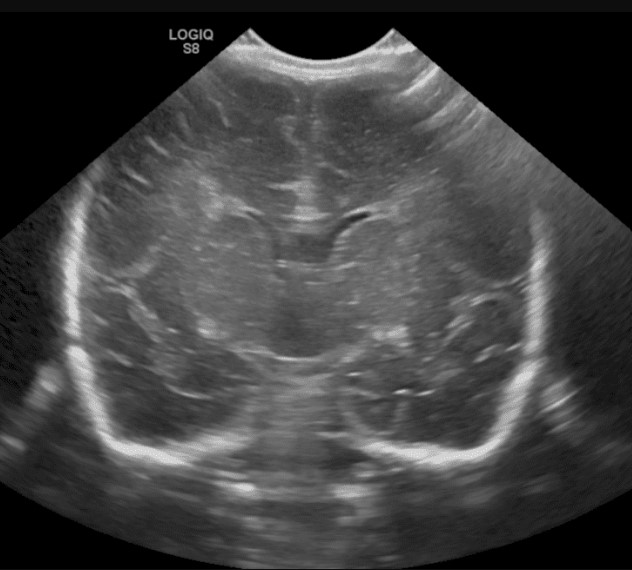

BT (Bilgisayarlı Tomografi) ile MRI farkı nedir?

BT, röntgen ışınları kullanılarak yapılan bir testtir. Beynin görüntülemesinde MRI kadar detaylı olmasa da hızlı yapılabilme avantajı vardır. Günümüzdeki yeni sistemlerde dakikalar içinde BT yapılabilir. Hasta uyumu daha kolaydır. Kafatası ve kemik yapılar hakkında da MRI'a tercih edilir. Kanamayı da saptamada MR'dan hassastır. Özellikle acil görüntüleme gerektiğinde (travma, kanama, beyin ödemi gibi) çok kullanışlıdır.

BT'deki röntgen ışınları tehlikeli midir?

Röntgen ışınlarına yüksek dozda veya sık maruz kalındığında dokuda zararlı yan etkiler oluşabilir. Bu nedenle gebelikte kullanılması ve çocuklarda sık başvurulması önerilmez. Yeni sistemlerde kullanılan röntgen ışınları rutin bir akciğer filmi görüntülemesine muadil olduğundan önemli bir tehlike yaratmaz.